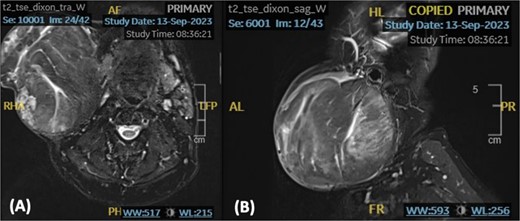

We present a case of a medically free sixty-nine-year-old male patient who presented to the otolaryngology outpatient department with a complaint of right-sided infra-auricular neck mass. The patient claims that the neck mass has been present for more than ten years; however, it has increased in size over the past four months prompting him to seek medical attention. Upon further history taking, the mass was slowly progressive, painless, and not associated with trismus, facial asymmetry, signs of inflammation, or other neck mass. On examination, the patient was vitally stable and looking well, with a nontender right-sided neck mass extending from the tail of the parotid superiorly up to the level of the cricoid inferiorly. The mass was well-defined, mobile, and multilobulated, approximately measuring 10 × 10 cm in size. A T2-Weighted Fast Spin Echo (FSE) noncontrast magnetic resonance imaging (MRI) of the neck demonstrated a large discrete rounded heterogeneous lesion, with soft tissue signal, noted at the right parotid region measuring 11.5 × 10.5 × 11.5 cm in anteroposterior, transverse, and cranial planes, respectively (Fig. 1). A significant mass effect on adjacent structures causing elevation and stretching of the overlying neck skin, sternocleidomastoid, submandibular gland, and masseter muscle was noted. However, the right mandible appears preserved with no lymph node involvement.

An axial (A) and sagittal (B) T2-weighted MRI showing a rounded well-defined heterogeneous lesion with soft tissue signal.